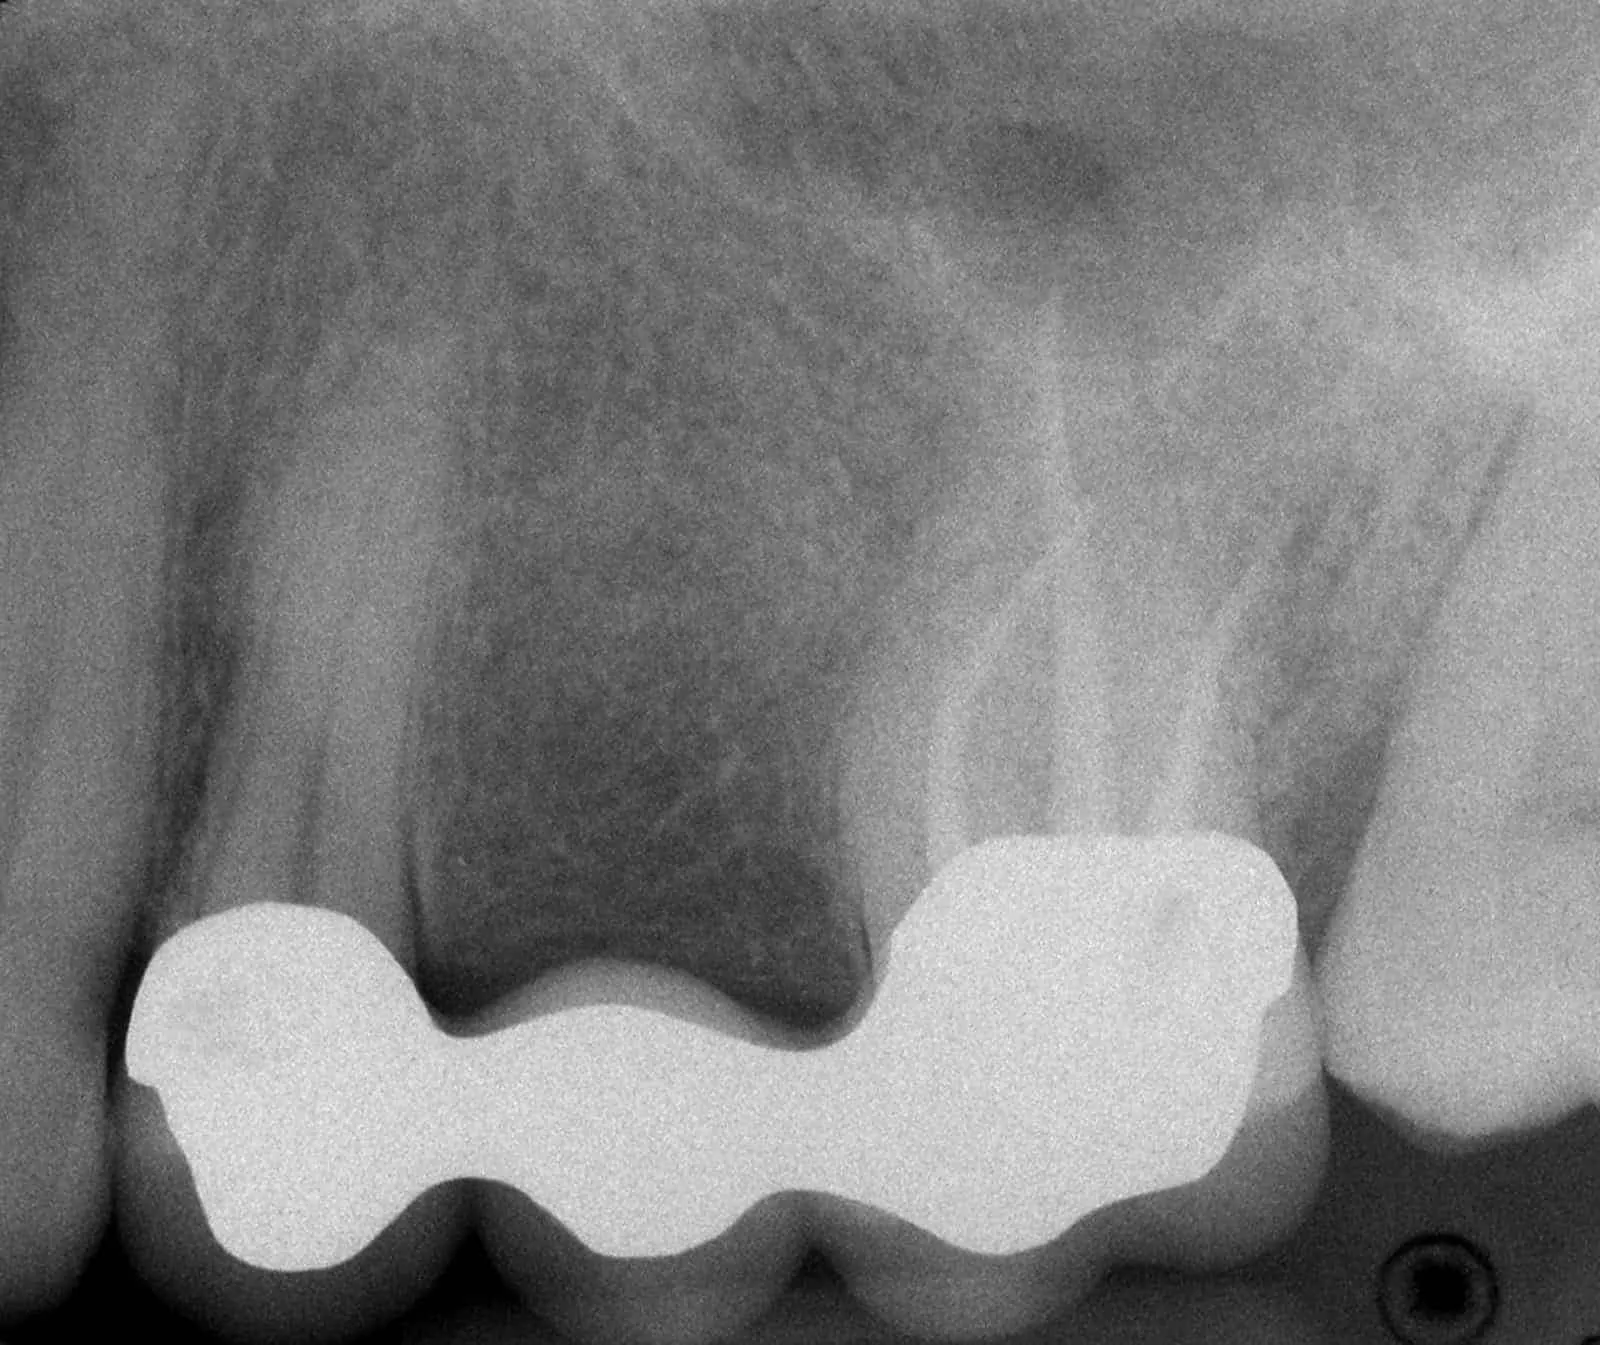

Before:Â Failed upper posterior three-unit bridge. Tooth #14 (upper left first molar) requires root canal therapy. Ideal candidate for a single dental implant to replace missing tooth #13 (upper left second premolar) and two single crowns on abutment/support teeth 12 (upper left first premolar) and 14. However, the patient is not interested in implant therapy and would like revision crown and bridge (fixed partial denture) therapy.

After:Â Revision crown and bridge therapy. Tooth #14 was carious and required root canal therapy and a build-up (foundation restoration) prior to definitive bridge therapy. Three-unit fixed partial denture (bridge), porcelain fused to gold, abutment teeth 12 and 14.